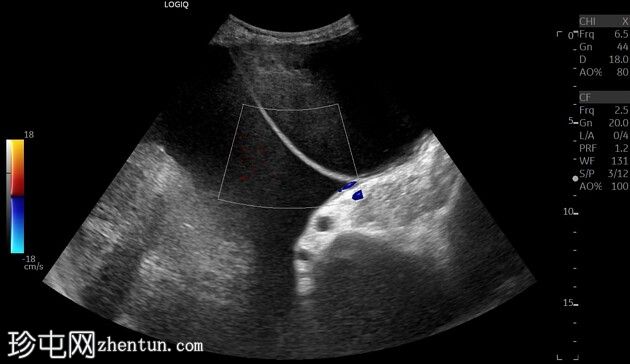

盆腹腔内有一大型双房性囊性病变,大小约为245(横向)x 230(头尾向)x 113(前后向)毫米,估计体积为3376毫升。囊肿内容物无回声,无实性成分、乳头状突起、囊壁不规则或阴影。囊隔内无血流。病变从盆腔延伸至上腹部,并向两侧腹壁外侧延伸。未见相关腹水或腹部淋巴结肿大。子宫萎缩,双侧卵巢无法定位。

右侧轻度肾积水。左肾皮质单纯性囊肿,无肾积水。左叶肝单纯性囊肿。膀胱、脾脏、胰腺和胆囊均正常。

超声检查发现一位腹胀的老年患者腹盆腔内有一处大型囊性病变。该病变疑似良性卵巢病变。患者此前(20个月前)的超声检查也发现了类似的病变。然而,病变体积从最初的2325cc增大到目前的3376cc。

之后的CT扫描也发现了类似的结果。手术后发现病变源自左侧卵巢。组织病理学诊断为卵巢浆液性囊腺瘤。